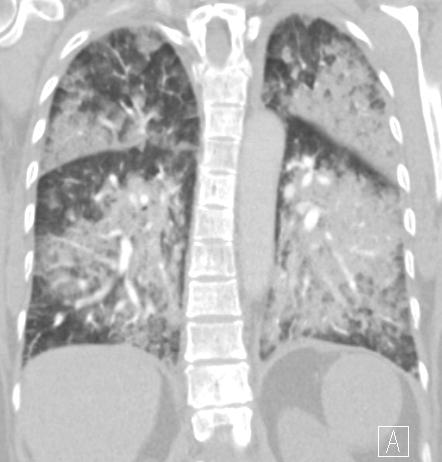

ground-glass opacities mixed with consolidation; typically the GGO forms the edge of the opacities

spared costophrenic angles

prominent septal lines only in the area of the GGO indicating, the subacut phase, when resolution begins; opacities are mainly gravity dependent

partial resolution in a few days